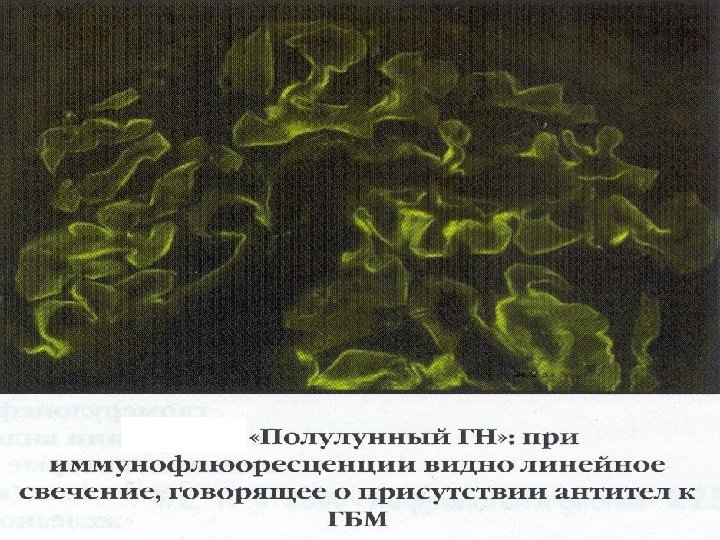

Лабораторные методы обследования Иммунология § АСЛО, СРБ при остром гломерулонефрите § комплемент, АНФ, LE-клетки, Ig A, M, G при системной красной волчанке (СКВ) § АНЦА при гранулематозе Вегенера; § антитела к базальной мембране при синдроме Гудпасчура; § антитела к кардиолипинам при антифосфолипидном синдроме; § маркеры HBV и HCV, криоглобулины при гепатитах и циррозах